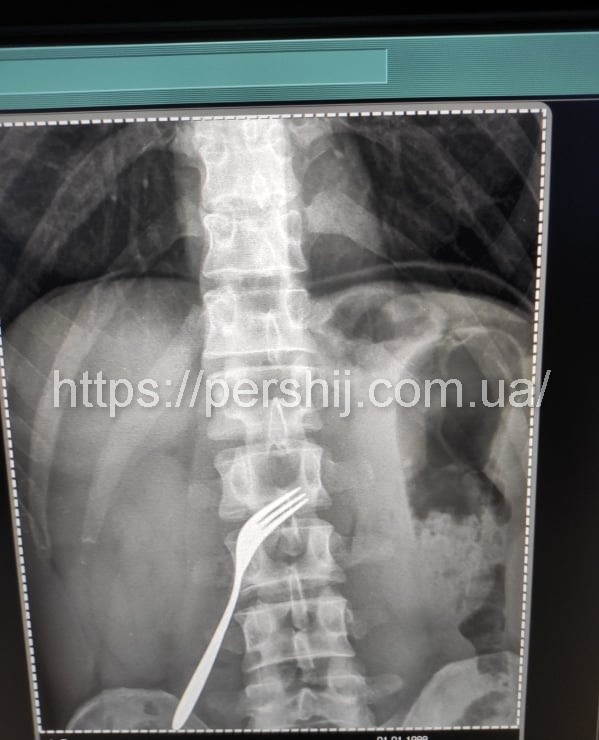

Нещасний випадок в Ужгороді: чоловік проковтнув виделку (ФОТО)

В обласному центрі Закарпаття чоловік проковтнув виделку. Сторонній предмет з тіла чоловіка довелося витягати лікарям.

Оперативне втручання здійснювали медики Ужгородської міської клінічної лікарні. Пацієнта прооперували вчора, 8 липня.

За словами головного лікаря Ужгородської міської клінічної лікарні Івана Кураха, сторонній предмет пацієнт проковтнув близько 3-4 місяців тому. Декілька днів тому стан хворого погіршився. Виделка уразила слизову шлунку. Саме тоді вже звернулися за допомогою медиків. До слова, чоловік, що проковтнув сторонній предмет, має психічні розлади.